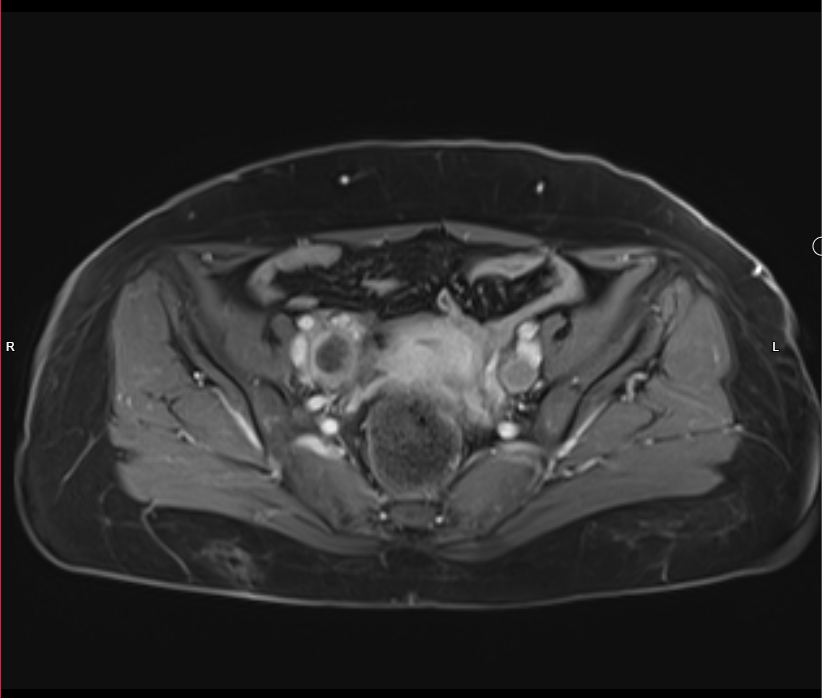

Pelvic MRI With IV Gd:

- Evidence of 7.5 X 4cm mass involves Rt side of uterus reaches endometrium, involves whole thickness of uterus and extends to Rt adnexa, also infiltration of peritoneal reflesion in Rt side of rectouterine pouch, shows marked DWI restriction, picture is suggestive of malignant tumor ?lymphoma ?sarcoma

- Single Lt internal iliac pathological LN, 18mm in short axis diameter, its signal is like uterine mass.

- There is also 26 X 22mm lesion in Rt internal iliac region, but heterogeneous signal ?pathological LN with necrosis

- Endometrial thickness is 8 mm, no obvious focal mass.

- Mild pelvic free fluid.

- Normal both ovaries in size, no mass.

- Normal UB in wall thickness.

- No obvious rectal pathology.

- No pelvic bone lesion.